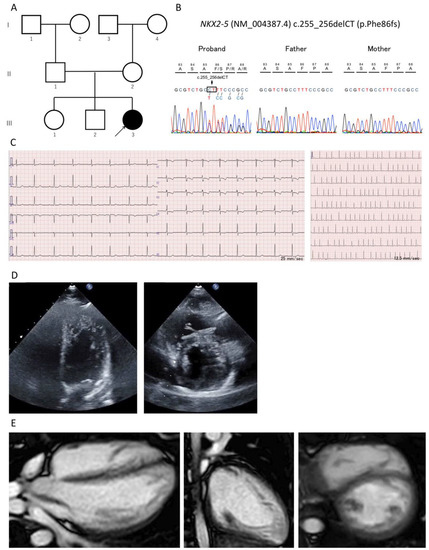

A Novel NKX2-5 Variant in a Child with Left Ventricular Noncompaction, Atrial Septal Defect, Atrioventricular Conduction Disorder, and Syncope

2. Case Presentation

| Present case | 2022 | 12 | F | c.255_256delCT | p.Phe86fs | deletion | frameshift | LVNC | ASD | IAVB | yes | no | no | no | no |